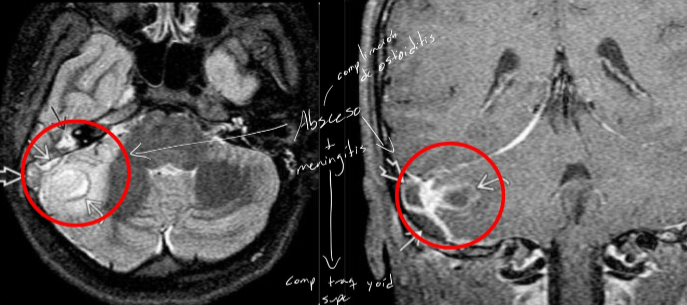

como se ve en RM mastoiditis

How well did you know this?

Mastoiditis / Otomastoiditis

infección de la apofisisi mastoides (cronica o aguda)

- cronica: resorción ósea y desmineralización

- complicacion de la otitis